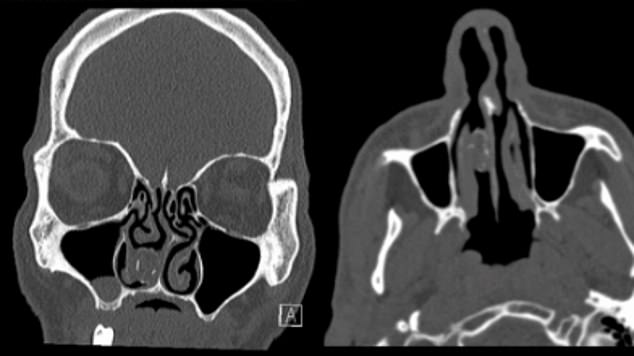

Các bác sĩ ở Úc đã tiến hành chụp CT não, sau khi người đàn ông đến bệnh viện và phàn nàn về chứng đau đầu của mình - một trong những triệu chúng phổ biến của sỏi mũi. Qua ảnh chụp, các bác sĩ thấy một vết thương màu xám với kích thước 1,9cm x 1,1cm trong khoang mũi phải của anh ta. Sau đó anh ta được chuyển đến khoa tai mũi họng tại Bệnh viện Westmead, Sydney.

Hình chụp CT của người tù nhân “đãng trí”